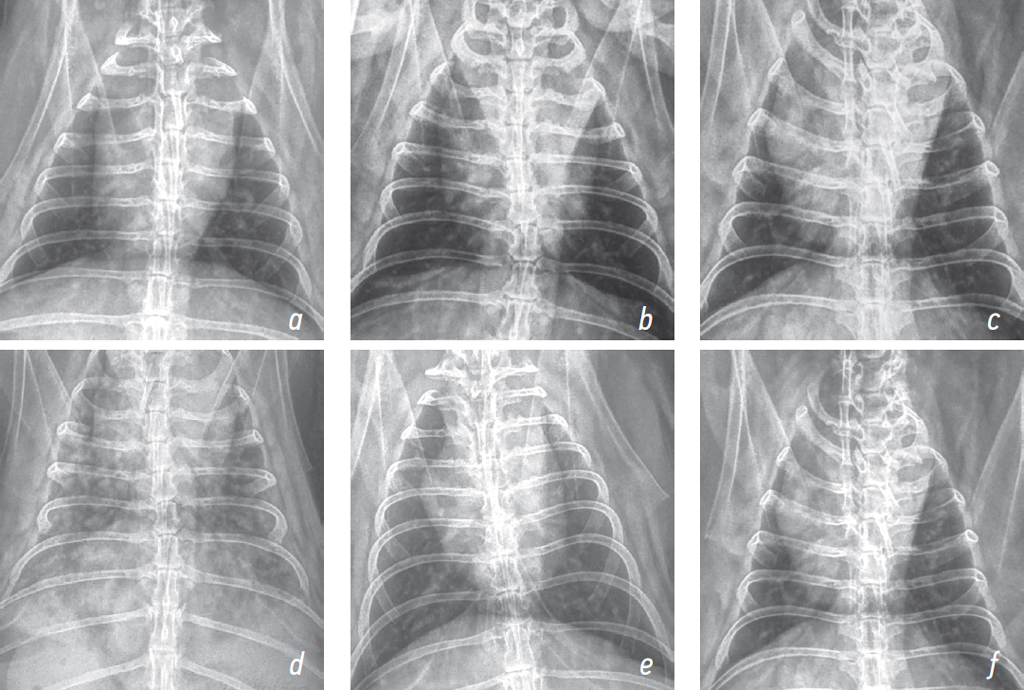

Plain chest radiography of rabbit 1 showed preserved lung fairness, normally visualized cardiovascular structures, smooth and clear diaphragmatic dome, and preserved cardiosternal contact. An hour after exposure, areas of interstitial shadowing and prominent bronchopulmonary pattern were noted on plain chest radiographs of rabbits 2 and 3 (Figs. 1 and 2).

Fig. 1. Radiographs of the chest organs of rabbits in a direct projection at various times after exposure to the thermal destruction products of fluoroplastic-4 (1,5 HLC50); a — rabbit 1 (control), b — rabbit 2 (intoxication, 1 hour), c — rabbit 3 (treatment, 1 hour), d — rabbit 2 (intoxication, 6 hours), e — rabbit 3 (treatment, 6 hours), f — rabbit 3 (treatment, 7 days)

Рис. 1. Рентгенограммы органов грудной клетки кроликов в прямой проекции в различные сроки после воздействия продуктов термодеструкции фторопласта-4 (1,5 HLC50); a — кролик 1 (контроль), b — кролик 2 (интоксикация, 1 ч), c — кролик 3 (лечение, 1 ч), d — кролик 2 (интоксикация, 6 ч), e — кролик 3 (лечение, 6 ч), f — кролик 3 (лечение, 7-е сут)

Radiography was performed 6 hours following exposure. Plain chest radiography of rabbit 2 showed diffuse alveolar opacities, most prominent in the middle and caudal lobes, and notable bronchopulmonary pattern. Plain chest radiography of rabbit 3 showed a moderately prominent bronchopulmonary pattern and normal lung airiness (Figs. 1 and 2).

On day 7 after exposure, the gas exchange parameters (i. e., SaO2, PetCO2, and OI) in rabbit 3 did not differ from background values. Plain chest radiography demonstrated normal lung airiness with no areas of interstitial shadowing (Figs. 1 and 2). Auscultation revealed no wheezing. After radiography, rabbits 3 and 1 were sacrificed and their lungs were removed.